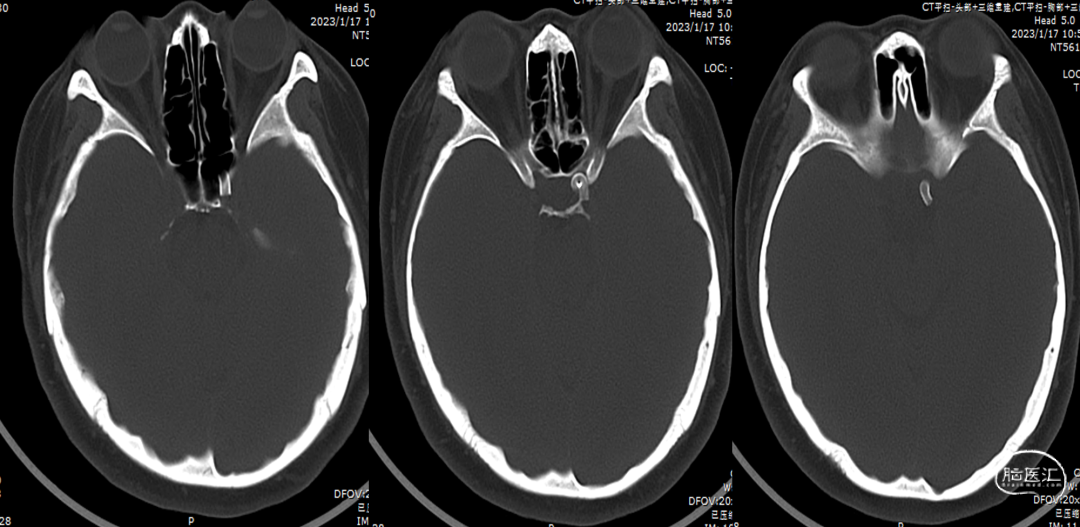

术后8个月复查CT(2022-12-25)

半年后第二次复查CT(2023-01-17)